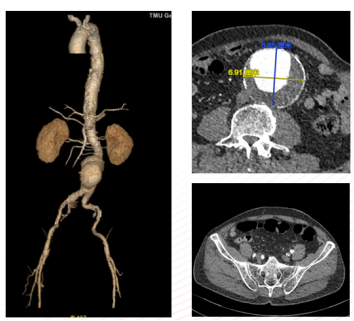

患者男,73岁,因“发现腹主动脉瘤3年余”入院。既往高血压、糖尿病史,长期吸烟。术前CTA显示肾下腹主动脉瘤,近端瘤颈充足,左侧髂内动脉狭窄,右侧正常。

造影示肾下腹主动脉瘤

选用28-14-140mm主动脉覆膜支架

患者女,66岁,腹主动脉瘤合并右髂外动脉闭塞。术中开通右侧髂外动脉,封堵右侧髂内动脉,保留左侧通畅髂内动脉。